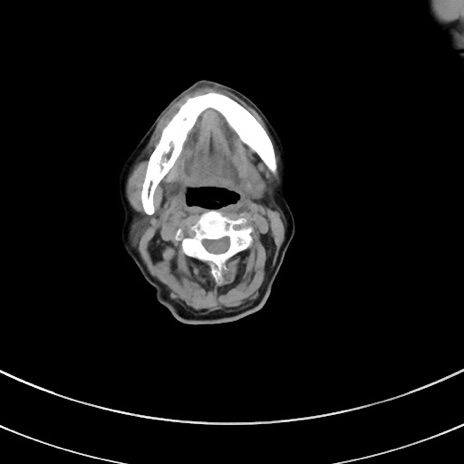

冠状断像